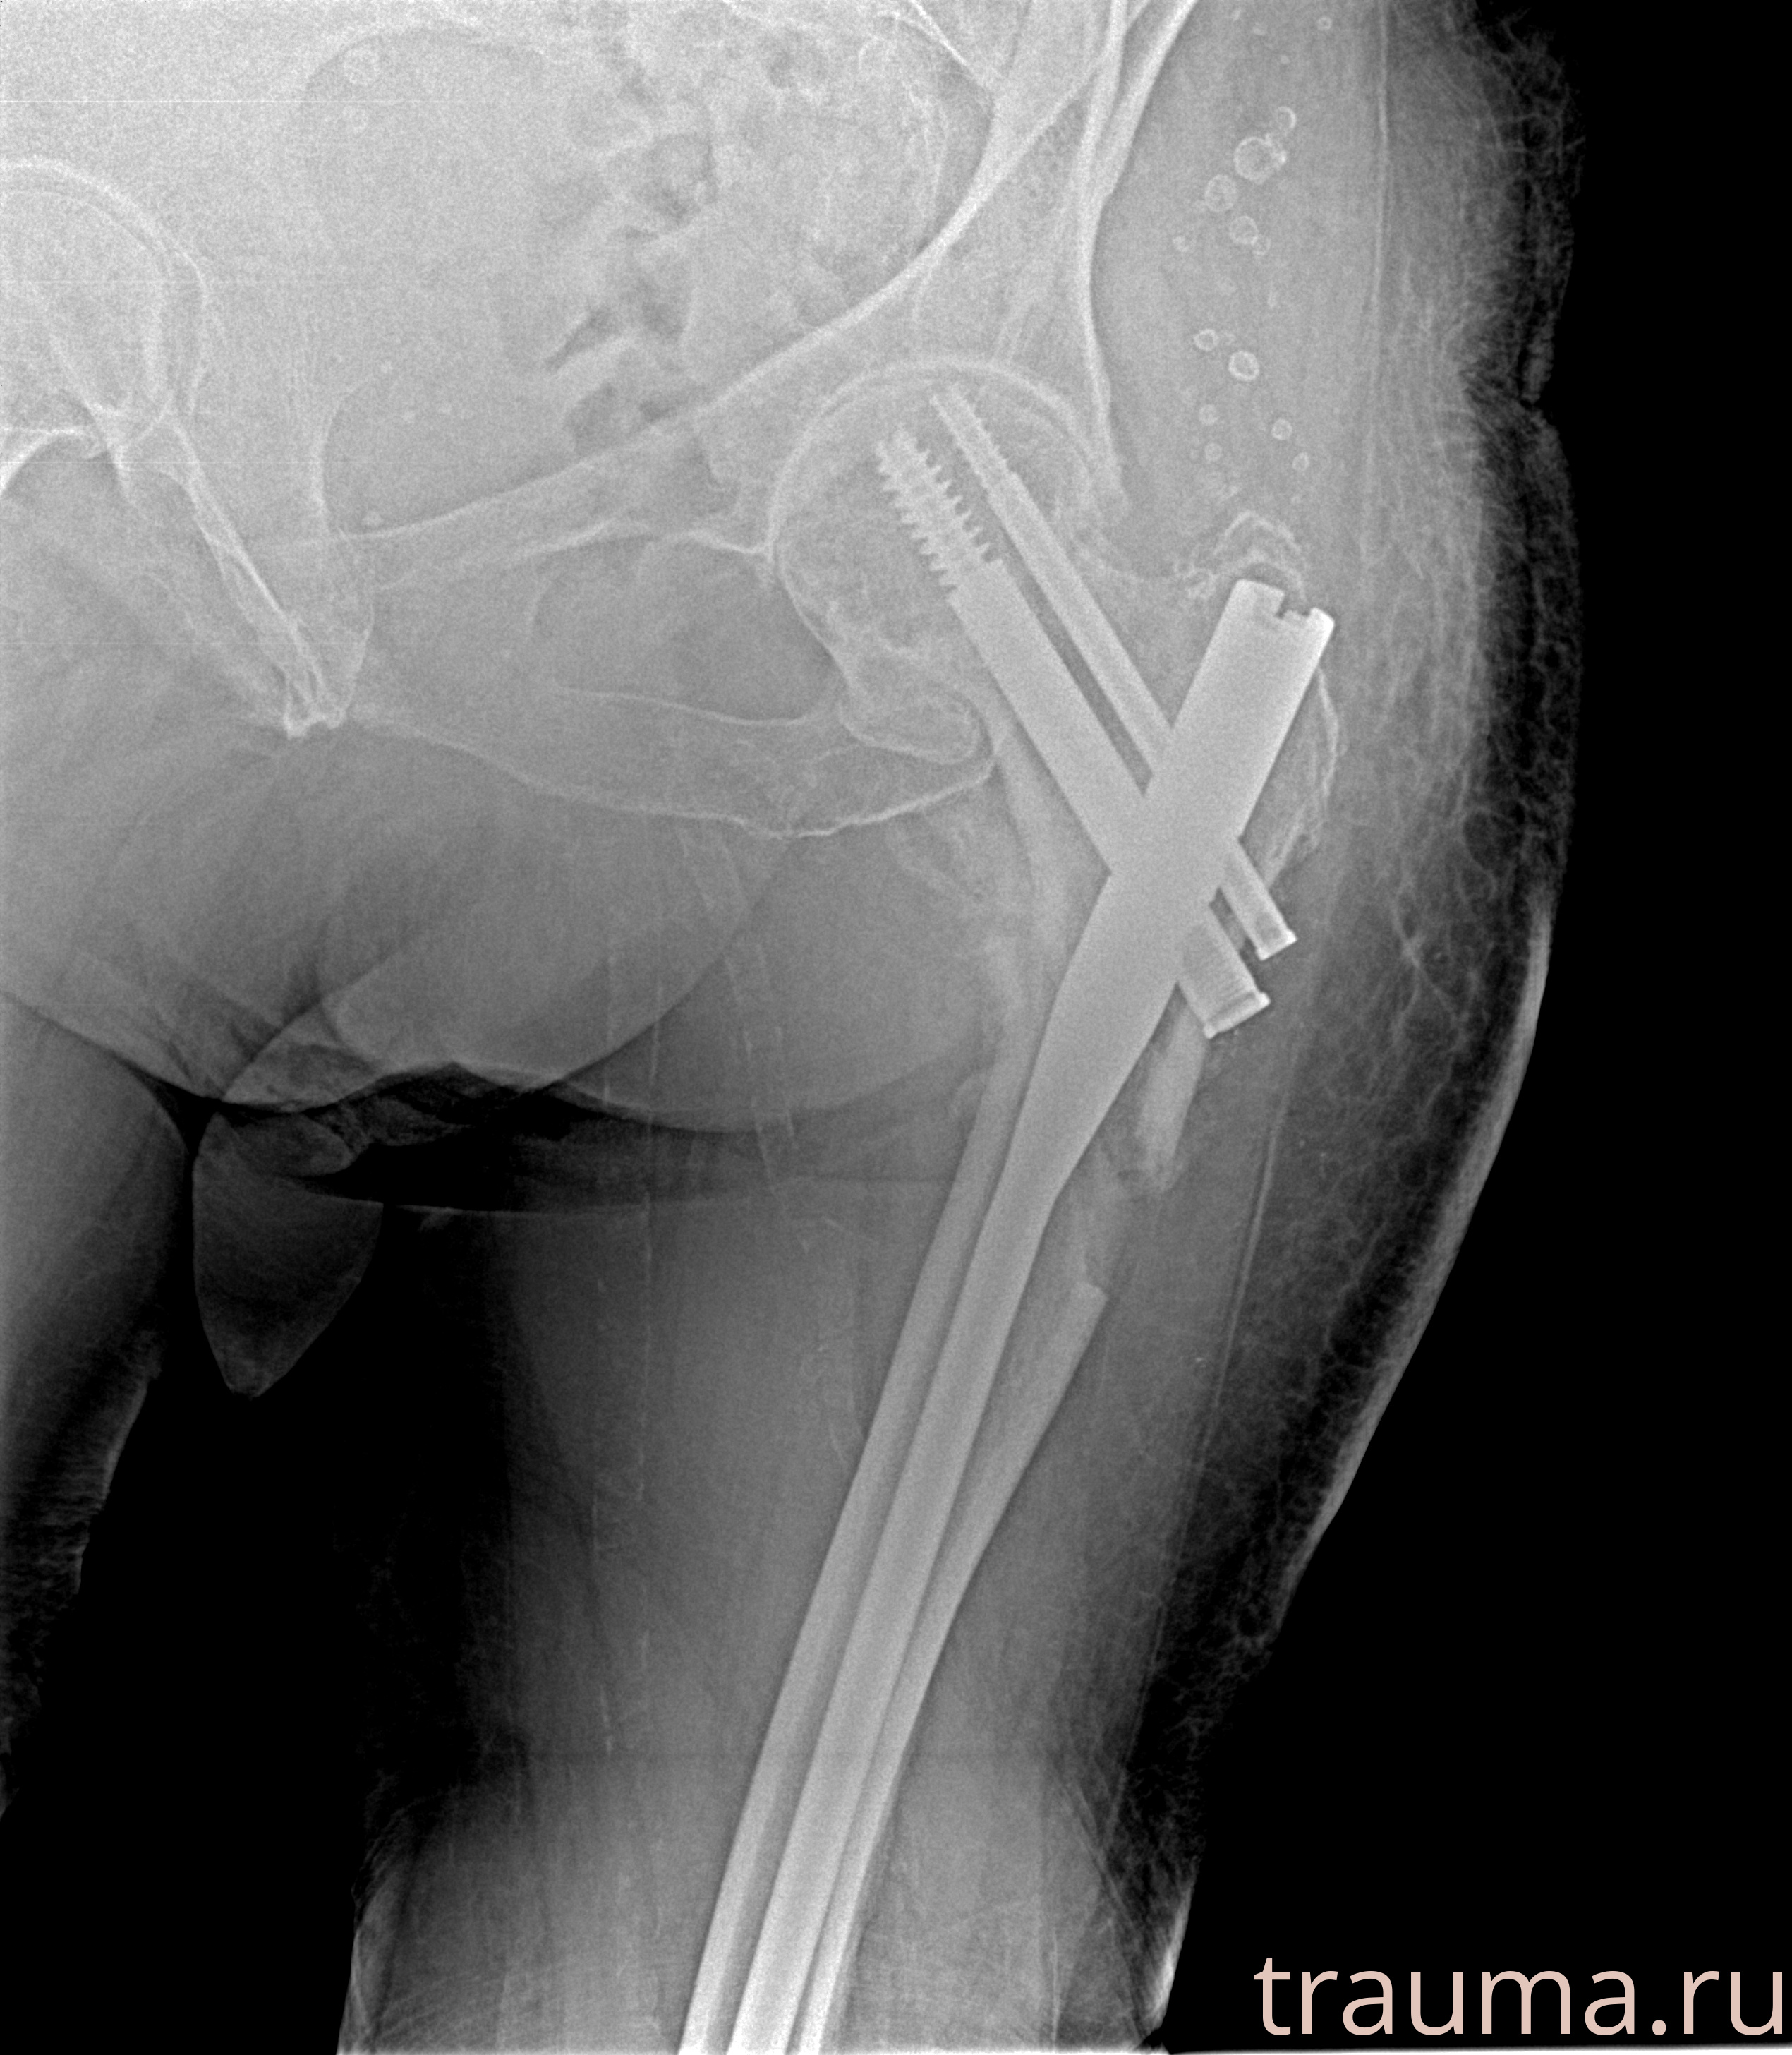

Рентгенограммы

Рентген на дому: по вашему адресу приезжает врач-рентгенолог, травматолог-ортопед с мобильным рентгеновским аппаратом, проводит диагностику травмы или заболевания, делает необходимые рентгенограммы, дает рекомендации по дальнейшему лечению. Получить качественные снимки в домашних условиях возможно благодаря уникальной методике, разработанной МосРентген Центром для института  Склифосовского